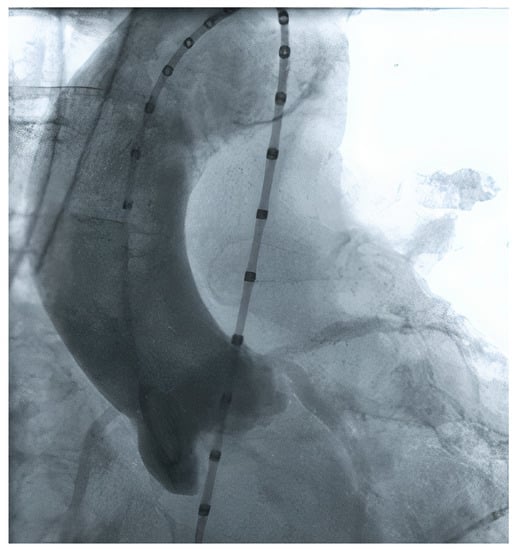

2.7. Peripheral Access Vessels